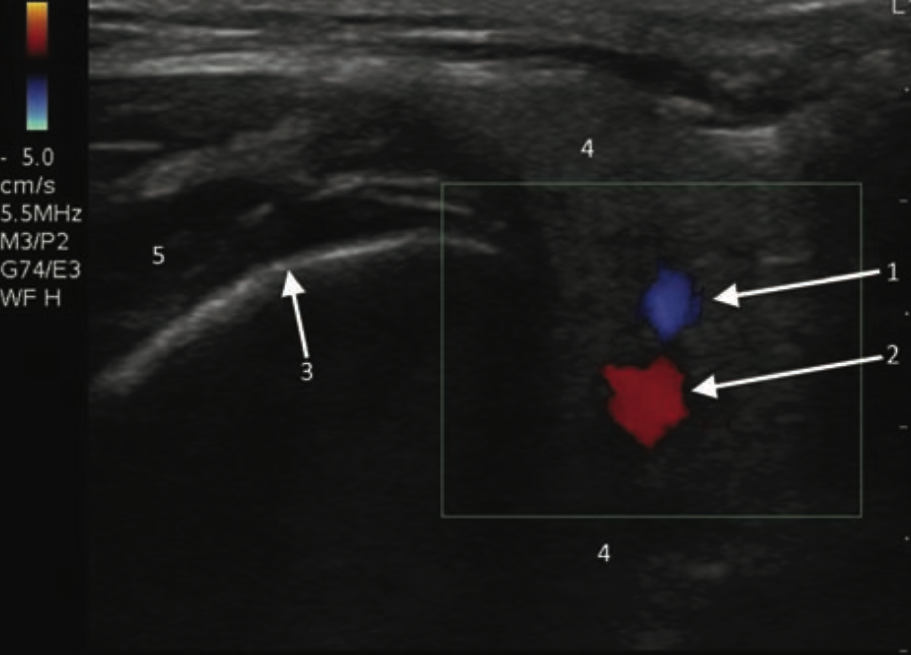

- Figure 15 and 16. Transverse view of normal left parotid gland with color doppler on vessels (1- Retromandibular vein; 2- External carotid artery; 3- Surface of the mandible; 4- Parotid gland; 5- Masseter muscle)